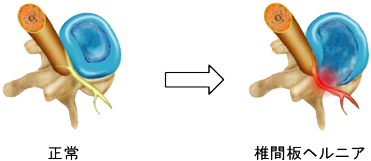

椎間板ヘルニア

背骨のクッションである椎間板の一部が飛び出し、神経を圧迫して腰や足に痛みやしびれ(坐骨神経痛)を引き起こす病気です。治療は、まず薬や注射、理学療法などの保存療法を行います。症状が強く改善しない場合や、足に麻痺がある場合、日常生活に支障がある場合には手術が検討されます。